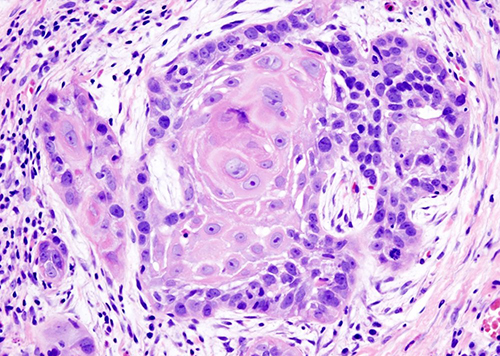

Профессор физики Техасского университета в Арлингтоне Вэй Чен совместно со своей командой разработал фотопрепарат от рака нового поколения. Речь идет о цистеамина меди. Недавно ученые представили две статьи, в которых подробно описали эффект препарата.

В статье, представленной в журнале Materials Today Physics, ученые рассказали о фотосенсибилизаторах цистеамина меди. Эти молекулы, для активации которых необходим свет, имеют люминисцентные свойства. За их счет производится больше активных кислородных форм. Они и убивают раковые клетки.

Второе исследование, представленное в журнале Bioactive Materials, показало, что фотодинамическая терапия на основе цистеамина влияет на пролиферацию и миграцию раковых клеток в условиях клинической имитации. Цистеамин меди смог подавить пролиферацию глубоко укоренившихся опухолевых клеток и свести к минимуму токсические побочные эффекты, связанные с лечением рака, влияющим на здоровые клетки.